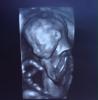

Фото в 20 недель в Ультрамеде дали это что-то😂😂😂Муж спросил - а где тут лицо? А я сама не знаю😱🙈в 24 недели фото было уже суперским!👍Правда в Семье, и мне кажется у них аппарат лучше все же🤗☝️

Были в ультрамед на Достоевского, все понравилось, только маленькая она ещё, фото пока не очень, да и оно там вроде как бонусом идёт вместе с видео. С сыном в первую беременность фото в 32 недели делали, очень даже похож был)